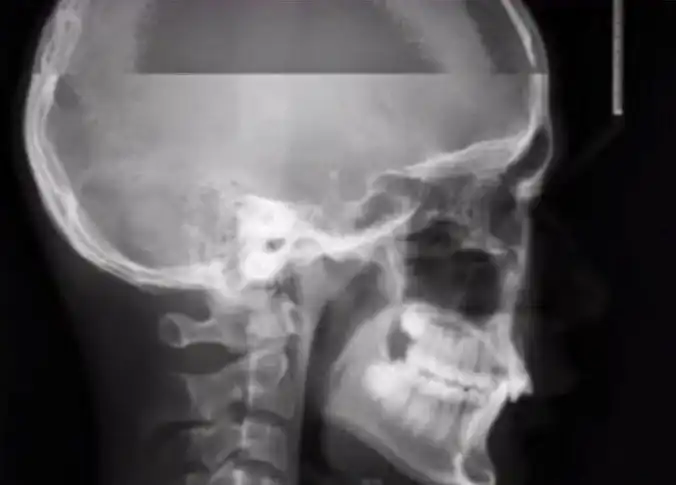

Вот так, как на этом фото, выглядит обычный рентген. А вы когда-то задумывались над тем, как будет выглядеть рентген, если пациент случайно чихнет во время создания снимка? Хотите взглянуть на то, что из этого вышло? Тогда смотрим.